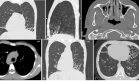

Los estudios de seguimiento han mostrado cambios estructurales en el sistema nervioso central, particularmente en la resonancia magnética cerebral que reveló atrofia cortical generalizada y atrofia hipocampal bilateral.